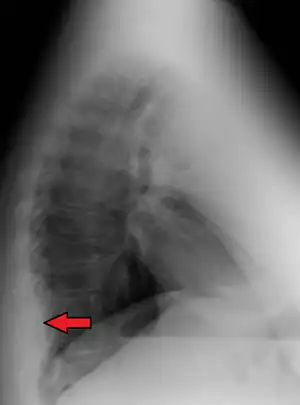

| Mediastinal lipomatosis | |